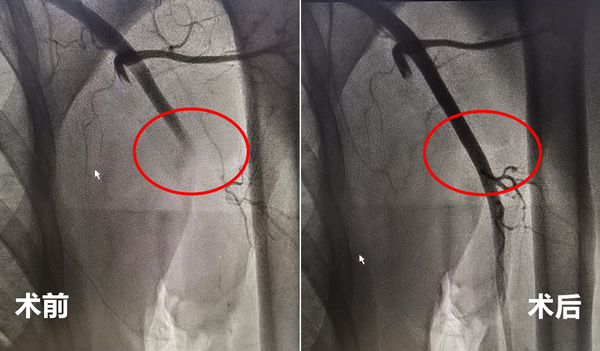

厦心心内科团队迅速展开急诊手术,既要清除血栓,又要防止血栓脱落继续向远端栓塞,还要精准将患者手臂的血流重新建立起来。不到一小时,大量暗红色血凝块经由导管被抽吸出体外,堵塞的血管及时恢复了畅通。患者紫色而冰凉的手臂逐渐变红温暖,血管充盈起来,疼痛症状也立即缓解,黄大叔紧锁的眉头终于舒展开来。